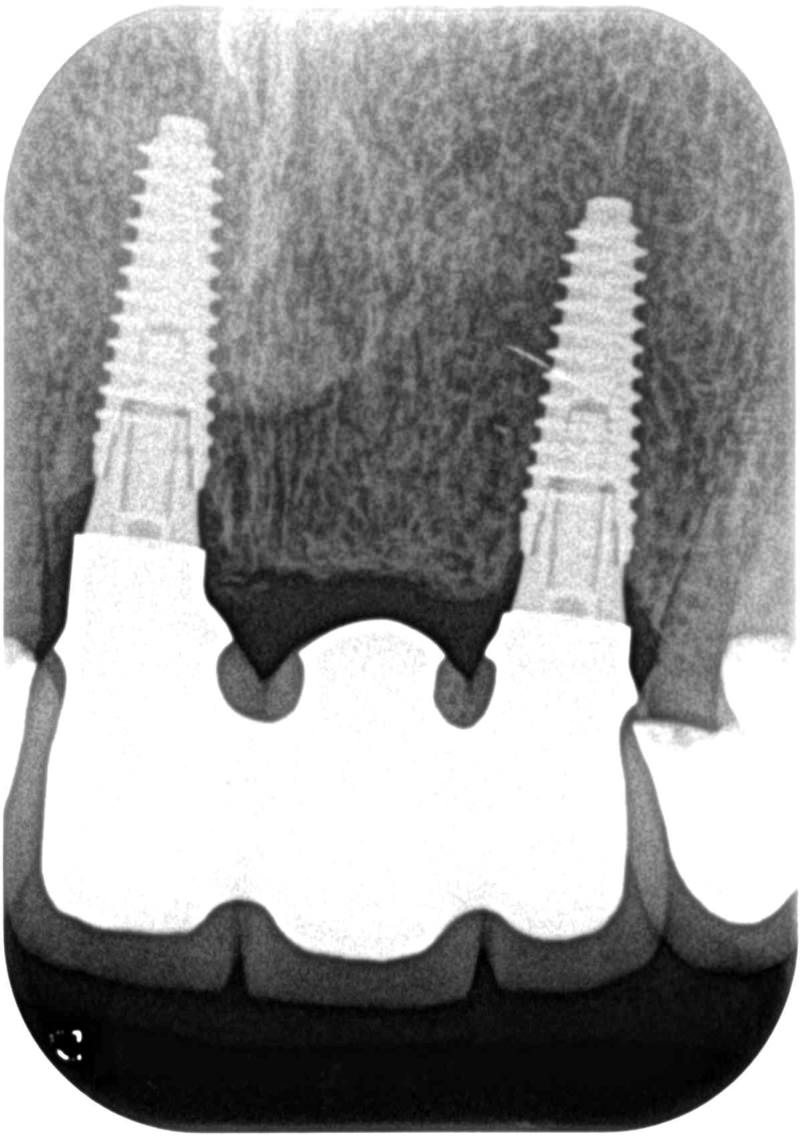

症例3【60代女性】主訴 審美障害・義歯がわずらわしい

治療前

治療後(3年経過)

治療後

主訴 上下の部分義歯が煩わしい、しっかり奥歯で噛めないと訴え来院。

上顎前歯部、左上臼歯部にはブリッジが装着されていて、支台歯に負担がかかっており、力学的配慮設計を重視し、固定制のインプラントを提案。

前歯部、小臼歯部には、造骨、歯肉移植も含めた幅の確保をし、永続性のある土壌作りを行った。

免荷期間中は、QOLを損なわない為に、ミニインプラント(即時荷重)を埋入、オペ当日に仮歯を装着し、咀嚼可能にした。

最終補綴物装着までの期間は、約8ヶ月を要した。ジルコニア(レイヤリング法)を装着。

リスクとしては、外科的侵襲がある。デメリットは、保険外診療の為、経済的負担がある。

費用 501万 (オペ・ミニインプラント・人工骨・歯肉移植・仮歯・採血による濃縮血小板生成・最終補綴物まで含む)